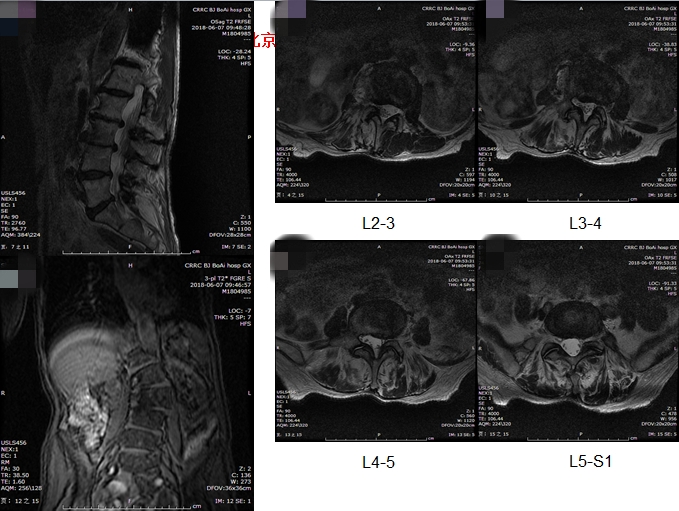

基本情况:女性,77岁,腰痛30年,加重一年,行走困难2月。身高158cm,体重190斤,就诊时轮椅推入病房。

影像检查:

洪毅教授:患者高龄,常年轻度慢性腰痛,本次加重1月余,无下肢神经功能损害,结合患者全长片、核磁体征表现,考虑患者疼痛加重原因为近期出现椎间关节损伤,需关注腰4-5,腰5-骶1节段。腰4-5小关节增生明显,椎间盘高度尚可,不能排除小关节骨关节病。腰5-骶1有ModicII期表现,可能为间盘源性疼痛来源,可进行诊断性封闭治疗。

孙常太教授:患者影像退变性骨关节病表现重,无椎管狭窄。虽有侧凸,但腰2-3,腰3-4侧弯节段可见明显的骨赘形成,稳定性强,腰5-骶1节段椎间盘高度已塌陷,亦较稳定,仅腰4-5节段仍有一定活动度,这就形成腰4-5节段的应力集中,体格检查压痛点与小关节位置亦吻合,需考虑重点关注此节段。

谭荣教授:同意孙教授意见,腰4-5节段动力位显示仍有一定活动度,同时腰4有I°滑脱,证明节段不稳定。病史中患者起身、刚下地时症状重亦支持节段不稳的表现。核磁腰4-5轴位可见明显的小关节病表现,Weishaup分级IV期,亦支持相关诊断。